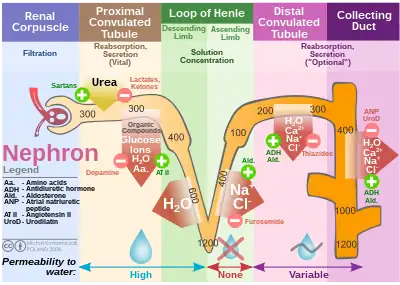

Diagram (left) of a long juxtamedullary nephron and (right) of a short cortical nephron. The left nephron is labelled with six named nephron segments. Also labelled is the collecting duct, mislabelled the "collection duct"; it is the last part of the nephron. | |

The nephron is the minute or microscopic structural and functional unit of the kidney. It is composed of a renal corpuscle and a renal tubule. The renal corpuscle consists of a tuft of capillaries called a glomerulus and a cup-shaped structure called Bowman's capsule. The renal tubule extends from the capsule. The capsule and tubule are connected and are composed of epithelial cells with a lumen. A healthy adult has 1 to 1.5 million nephrons in each kidney.[1]: 22 Blood is filtered as it passes through three layers: the endothelial cells of the capillary wall, its basement membrane, and between the foot processes of the podocytes of the lining of the capsule. The tubule has adjacent peritubular capillaries that run between the descending and ascending portions of the tubule. As the fluid from the capsule flows down into the tubule, it is processed by the epithelial cells lining the tubule: water is reabsorbed and substances are exchanged (some are added, others are removed); first with the interstitial fluid outside the tubules, and then into the plasma in the adjacent peritubular capillaries through the endothelial cells lining that capillary. This process regulates the volume of body fluid as well as levels of many body substances. At the end of the tubule, the remaining fluid—urine—exits: it is composed of water, metabolic waste, and toxins.

The interior of Bowman's capsule, called Bowman's space, collects the filtrate from the filtering capillaries of the glomerular tuft, which also contains mesangial cells supporting these capillaries. These components function as the filtration unit and make up the renal corpuscle. The filtering structure (glomerular filtration barrier) has three layers composed of endothelial cells, a basement membrane, and podocytes (foot processes). The tubule has five anatomically and functionally different parts: the proximal tubule, which has a convoluted section the proximal convoluted tubule followed by a straight section (proximal straight tubule); the loop of Henle, which has two parts, the descending loop of Henle ("descending loop") and the ascending loop of Henle ("ascending loop"); the distal convoluted tubule ("distal loop"); the connecting tubule, and the last part of nephron the collecting ducts. Nephrons have two lengths with different urine-concentrating capacities: long juxtamedullary nephrons and short cortical nephrons.

The four mechanisms used to create and process the filtrate (the result of which is to convert blood to urine) are filtration, reabsorption, secretion and excretion. Filtration or ultrafiltration occurs in the glomerulus and is largely passive: it is dependent on the intracapillary blood pressure. About one-fifth of the plasma is filtered as the blood passes through the glomerular capillaries; four-fifths continues into the peritubular capillaries. Normally the only components of the blood that are not filtered into Bowman's capsule are blood proteins, red blood cells, white blood cells and platelets. Over 150 liters of fluid enter the glomeruli of an adult every day: 99% of the water in that filtrate is reabsorbed. Reabsorption occurs in the renal tubules and is either passive, due to diffusion, or active, due to pumping against a concentration gradient. Secretion also occurs in the tubules and collecting duct and is active. Substances reabsorbed include: water, sodium chloride, glucose, amino acids, lactate, magnesium, calcium phosphate, uric acid, and bicarbonate. Substances secreted include urea, creatinine, potassium, hydrogen, and uric acid. Some of the hormones which signal the tubules to alter the reabsorption or secretion rate, and thereby maintain homeostasis, include (along with the substance affected) antidiuretic hormone (water), aldosterone (sodium, potassium), parathyroid hormone (calcium, phosphate), atrial natriuretic peptide (sodium) and brain natriuretic peptide (sodium). A countercurrent system in the renal medulla provides the mechanism for generating a hypertonic interstitium, which allows the recovery of solute-free water from within the nephron and returning it to the venous vasculature when appropriate.

The nephron uses four mechanisms to convert blood into urine: filtration, reabsorption, secretion, and excretion.[4]: 395–396 These apply to numerous substances. The structure and function of the epithelial cells lining the lumen change during the course of the nephron, and have segments named by their location and which reflects their different functions.

Proximal tubule

The proximal tubule as a part of the nephron can be divided into an initial convoluted portion and a following straight (descending) portion.[11] Fluid in the filtrate entering the proximal convoluted tubule is reabsorbed into the peritubular capillaries, including 80% of glucose, more than half of the filtered salt, water and all filtered organic solutes (primarily glucose and amino acids).[4]: 400–401

Loop of Henle

The loop of Henle is a U-shaped tube that extends from the proximal tubule. It consists of a descending limb and an ascending limb. It begins in the cortex, receiving filtrate from the proximal convoluted tubule, extends into the medulla as the descending limb, and then returns to the cortex as the ascending limb to empty into the distal convoluted tubule. The primary role of the loop of Henle is to enable an organism to produce concentrated urine, not by increasing the tubular concentration, but by rendering the interstitial fluid hypertonic.[1]: 67

Considerable differences aid in distinguishing the descending and ascending limbs of the loop of Henle. The descending limb is permeable to water and noticeably less permeable to salt, and thus only indirectly contributes to the concentration of the interstitium. As the filtrate descends deeper into the hypertonic interstitium of the renal medulla, water flows freely out of the descending limb by osmosis until the tonicity of the filtrate and interstitium equilibrate. The hypertonicity of the medulla (and therefore concentration of urine) is determined in part by the size of the loops of Henle.[1]: 76

Unlike the descending limb, the thick ascending limb is impermeable to water, a critical feature of the countercurrent exchange mechanism employed by the loop. The ascending limb actively pumps sodium out of the filtrate, generating the hypertonic interstitium that drives countercurrent exchange. In passing through the ascending limb, the filtrate grows hypotonic since it has lost much of its sodium content. This hypotonic filtrate is passed to the distal convoluted tubule in the renal cortex.[1]: 72

Distal convoluted tubule

The distal convoluted tubule has a different structure and function to that of the proximal convoluted tubule. Cells lining the tubule have numerous mitochondria to produce enough energy (ATP) for active transport to take place. Much of the ion transport taking place in the distal convoluted tubule is regulated by the endocrine system. In the presence of parathyroid hormone, the distal convoluted tubule reabsorbs more calcium and secretes more phosphate. When aldosterone is present, more sodium is reabsorbed and more potassium secreted. Ammonia is also absorbed during the selective reabsorption. Atrial natriuretic peptide causes the distal convoluted tubule to secrete more sodium.

Collecting duct system

Each distal convoluted tubule delivers its filtrate to a system of collecting ducts, the first segment of which is the connecting tubule. The collecting duct system begins in the renal cortex and extends deep into the medulla. As the urine travels down the collecting duct system, it passes by the medullary interstitium which has a high sodium concentration as a result of the loop of Henle's countercurrent multiplier system.[1]: 67

Though the collecting duct is normally impermeable to water, it becomes permeable in the presence of antidiuretic hormone (ADH). ADH affects the function of aquaporins, resulting in the reabsorption of water molecules as it passes through the collecting duct. Aquaporins are membrane proteins that selectively conduct water molecules while preventing the passage of ions and other solutes. As much as three-quarters of the water from urine can be reabsorbed as it leaves the collecting duct by osmosis. Thus the levels of ADH determine whether urine will be concentrated or diluted. An increase in ADH is an indication of dehydration, while water sufficiency results in a decrease in ADH allowing for diluted urine.[4]: 406